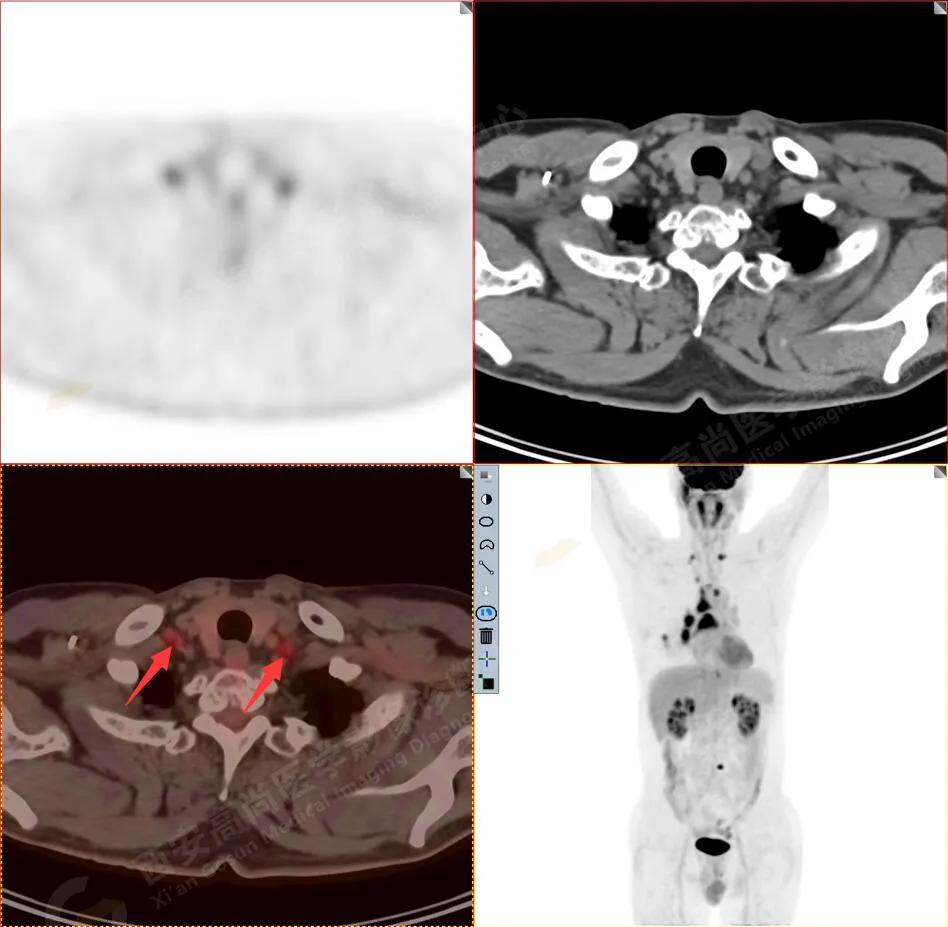

纵隔(1R\1L组)淋巴结转移

3.右侧肺门、纵隔(1L、1R、3A、4、6、7组)及双侧锁骨上多发肿大淋巴结,呈不同程度FDG代谢异常增高,考虑为淋巴结转移。